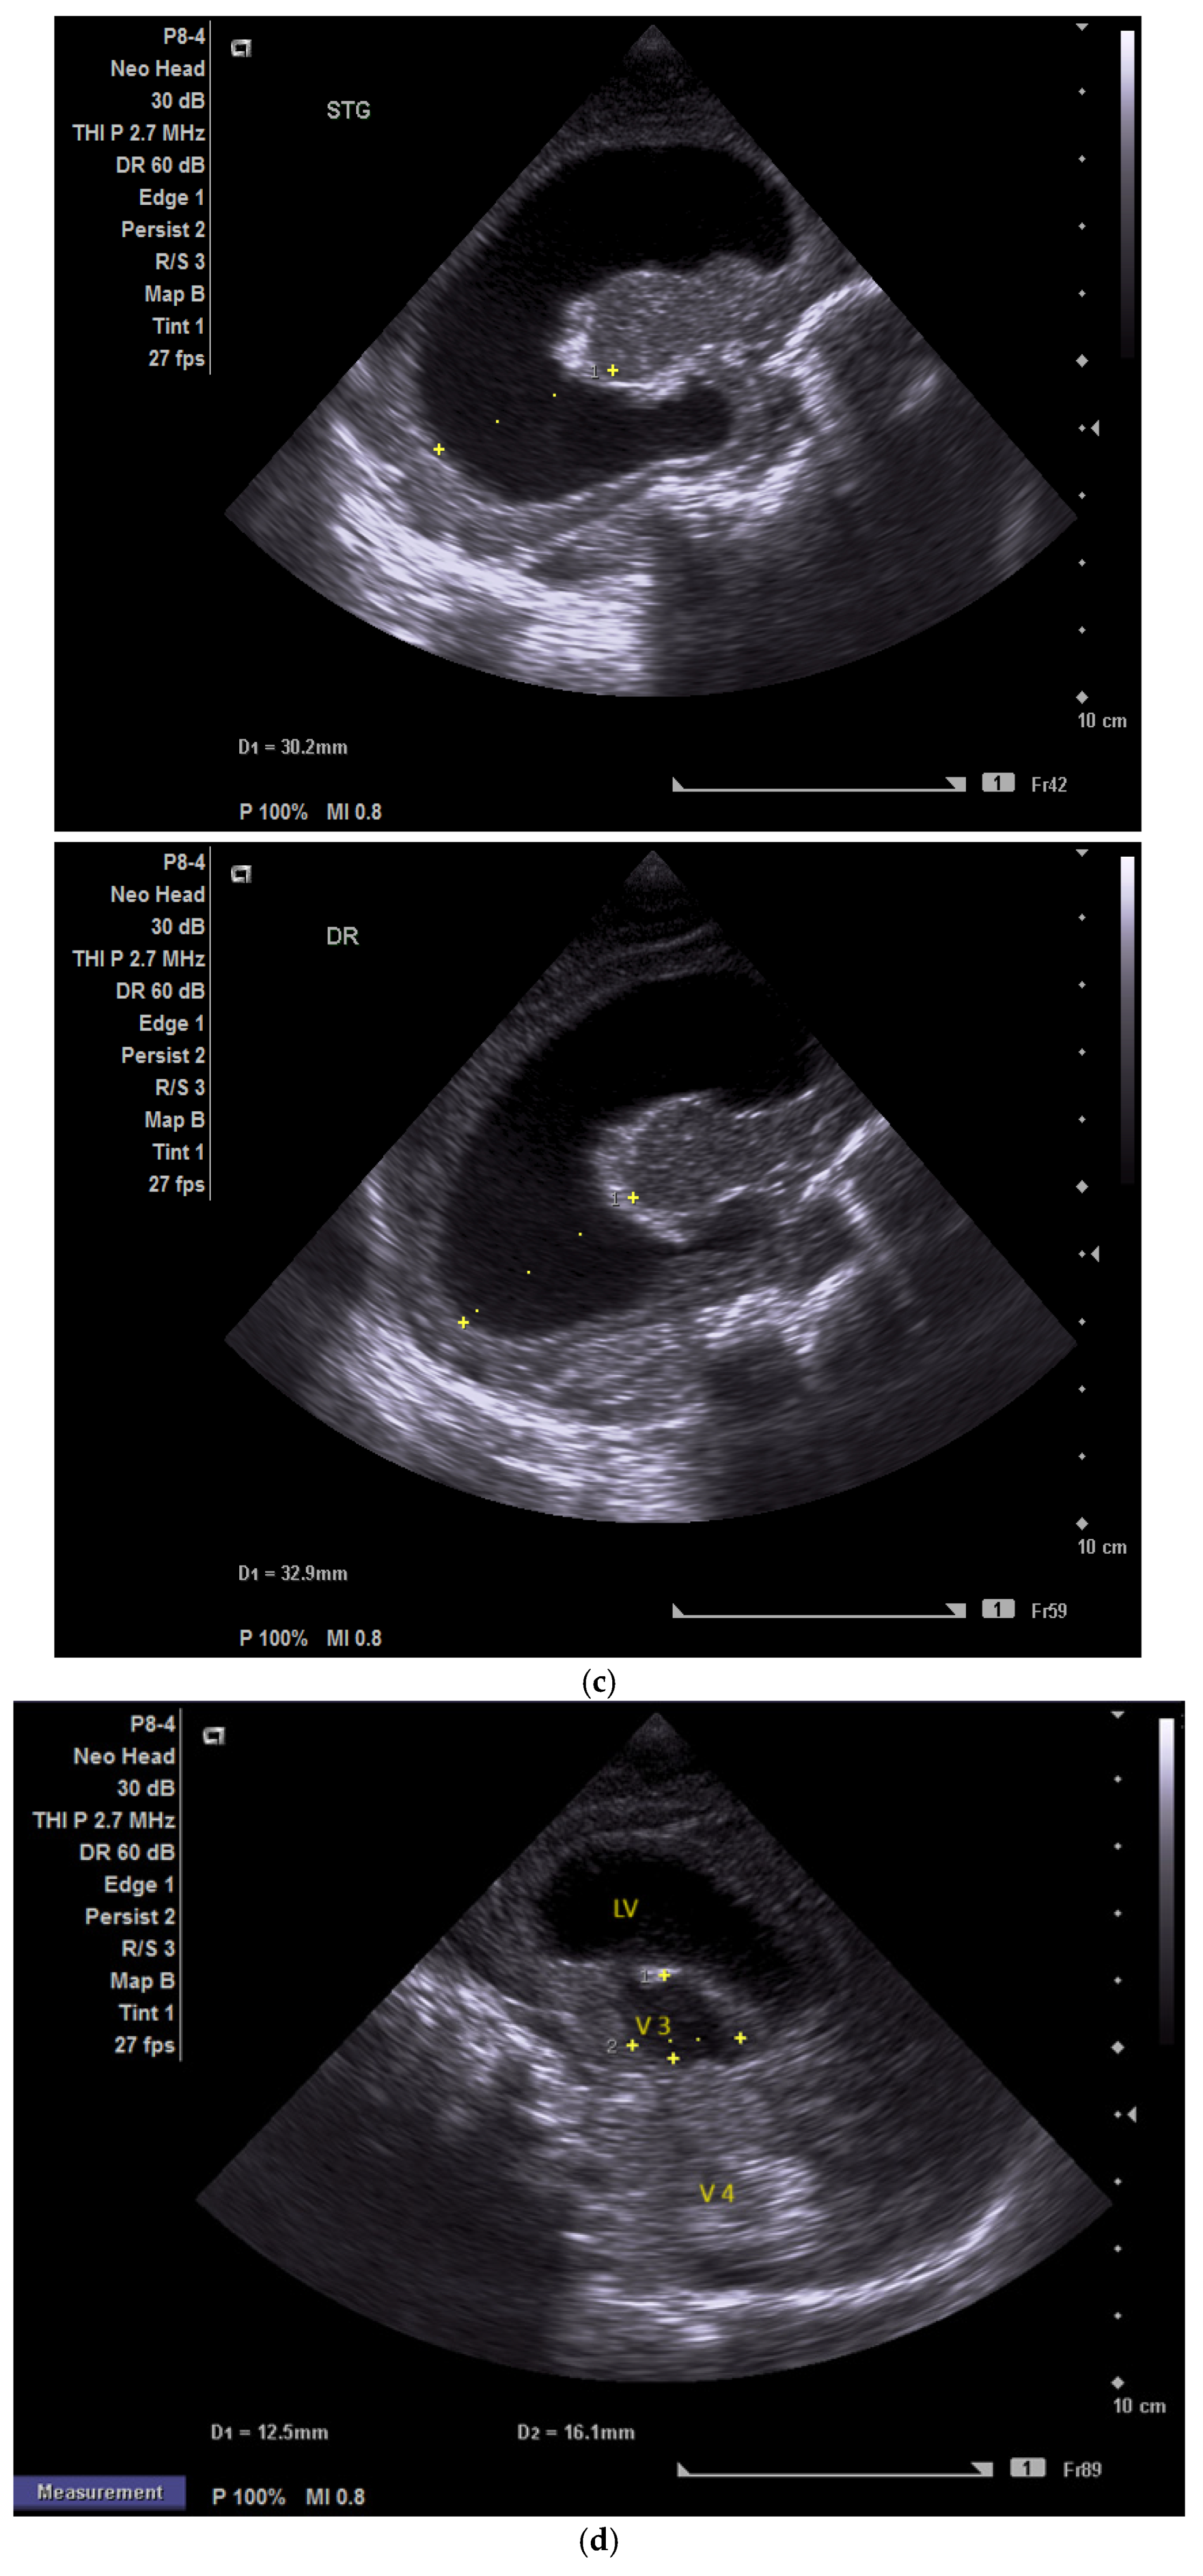

Case 5 involved a 35-week gestational age newborn who presented with birth asphyxia and required resuscitation after delivery, which involved a balloon and mask and then a balloon and laryngeal mask, and afterwards mechanical ventilation in the NICU (Neonatal Intensive Care Unit) with SIMV/IPPV (synchronized intermittent mandatory ventilation/invasive positive pressure ventilation), who was antenatally diagnosed through MRI with subacute polyhydramnios and ventriculomegaly due to a suspected medulla oblongata tumor (Figure 5a).

Figure 5.

(a,b) MRI—T2 sequence. Sagittal view. Antenatal. Yellow arrows indicate the place of the suspected tumor (personal image collection). (c) Cranial ultrasound. Sagittal view. Up—enlarged left ventricle. D1—thamalo-occipital distance. Down—enlarged right ventricle. D1—thalamo-occipital distance (personal image collection). (d) Cranial ultrasound. Sagittal view. Enlarged third ventricle. Fourth ventricle is normal. D1, D2—measurements of the third ventricle (personal image collection). (e) Cranial ultrasound. Transtemporal view. Enlarged third ventricle. Sylvian aqueduct is not visible. D1—measurement of third ventricle. LV AH—lateral ventricle anterior horn. LV OH—lateral ventricle occipital horn. V 3—third ventricle (personal image collection).

After stabilization, the cranial ultrasound exam revealed enlargement of the lateral ventricles and third ventricle, with a normal fourth ventricle. There was no visualization of the Sylvian aqueduct, which raised the suspicion of aqueduct atresia or stenosis (Figure 5c–e). There was no improvement seen in the cranial ultrasound examinations that followed.